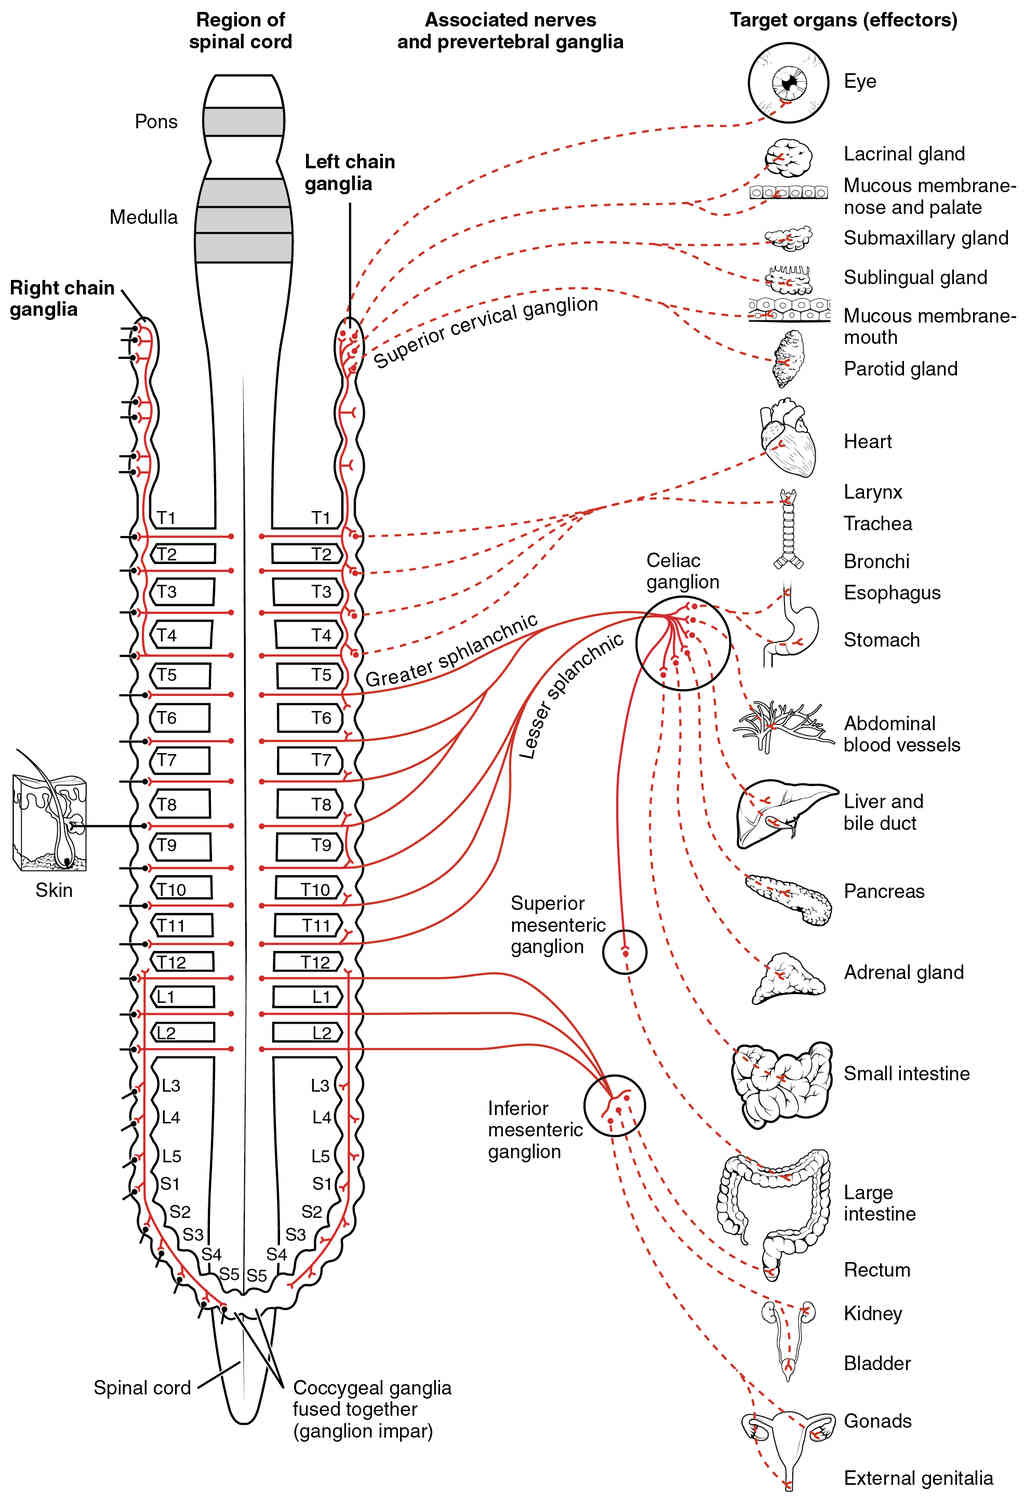

This page is under construction. For now, it is just a resource of the images found in the OpenStax Anatomy and Physiology Handbook. It wil slowly change into a revision tool. Each slide has a number. Use this to refer to the slide. When completed, it will have an unlabelled section, with labelled slides in parallel. On the unlabelled slides, write your answer and use the labelled slide to assess yourself. Keep track by also noting the number on each slide. Improvement at each attempt is important, more so than full marks on a first attempt.